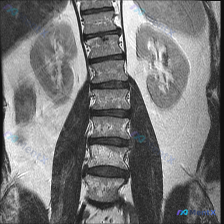

影像初看像脊柱侧弯?其实不是!这张MRI真正的阳性发现是什么

- 是一张腰椎+肾脏区域的T2加权冠状位MRI。

- 最初拿到资料时,有人先提了一句「会不会是脊柱侧弯」,但仔细看完影像报告和图像描述后,发现这个方向其实完全站不住脚。

- 这份影像是否存在脊柱侧弯?

- 真正值得关注的阳性发现是什么?